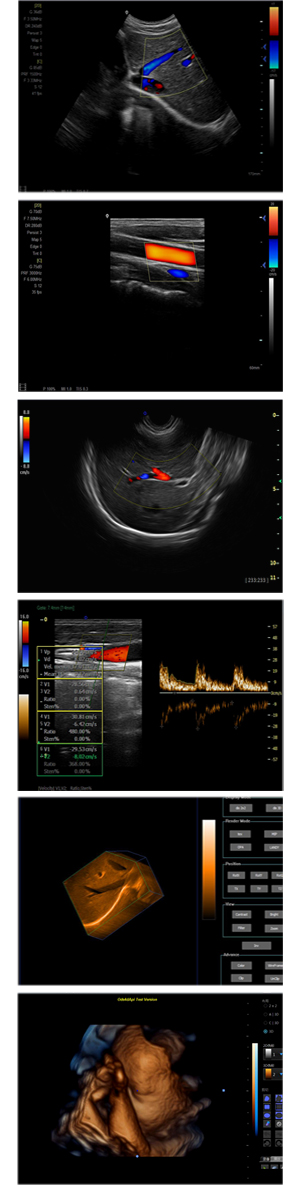

XF-7700型,秉承先鋒彩超技術之精華,擁有高雅大氣的獨特外型,為最新一代應用型數(shù)字彩色多普勒診斷系統(tǒng),魅力與實力相融合??蓮V泛適用于腹部、婦產(chǎn)科、心臟、小器官、乳腺、肌骨及外周血管等諸多方面的診查,讓您在臨床超聲診斷應用領域得心應手,綻放異彩!

突破的成像技術

● 3D/ 4D成像技術/選配

● 應用于腹部、腎臟、泌尿系統(tǒng)、產(chǎn)科、婦科、盆腔、大動脈、肌肉組織、小器官、乳腺、心臟等

● 能量多普勒成像(PDI)

● 彩色血流量圖(CDE)

● 脈沖頻譜多普勒成像(PW)